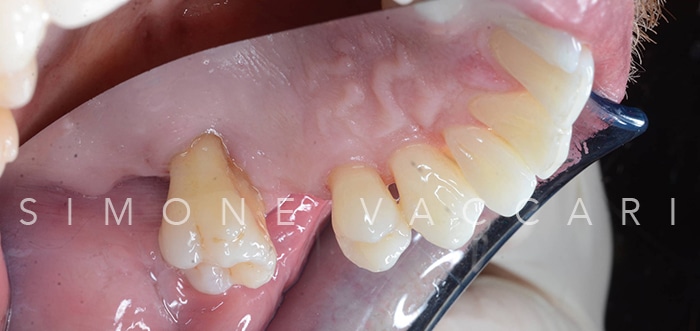

Michele bocca prima della cura della parodontite Prima

Michele arcata prima della cura della parodontite Prima